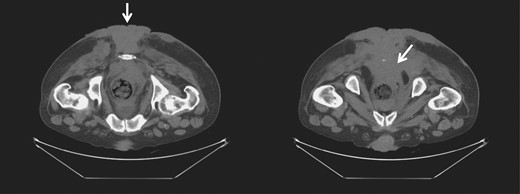

A 46-year-old male patient, of unknown sexual orientation, HIV-negative and history of alcohol abuse, was admitted to the hospital for diarrhea and purulent drainage of a foul-smelling, cauliflower-like lesion covering the bilateral buttocks. The patient had a history of multiple perianal condyloma acuminata that persistently recurred after a number of excisions and progressively enlarged over 20 years. On examination, a solid and fixed condylomatous lesion, measuring 27 × 20 cm2 (width × length) involved perineum, perianal area, and bilateral buttocks, from sacrum up to approximately the L4–L5 level. A fistula was also present along the right gluteal region, with the external opening measuring 2 cm in circumference and no signs of active infection. A computed tomography (CT) of the abdomen and pelvis showed a soft tissue density, measuring 14 × 11 × 17.7 cm3 (transverse × anteroposterior × craniocaudal), extending from the right posterolateral rectum, through the perirectal and presacral space, into the external buttocks (Fig. 1). Bilateral prominent inguinal lymph nodes were also noted. The colonoscopy showed involvement of the entire anal canal and rectum up to the distal sigmoid colon. The biopsy and histopathology showed condyloma acuminata with mild dysplasia and concluded a giant condyloma of Buschke and Löwenstein.

CT of the pelvis and perineum showing the BLT invading the rectum and anal canal.